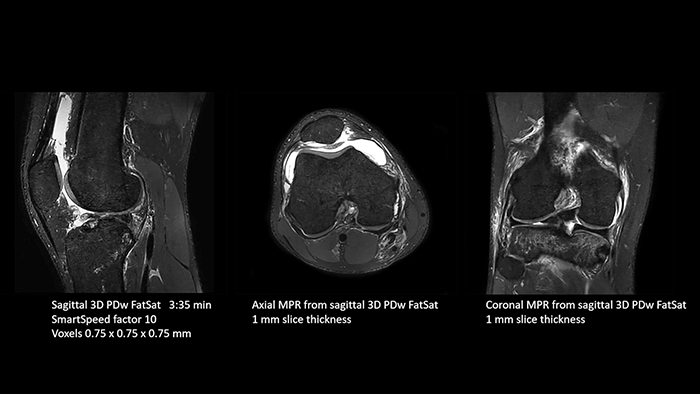

Previously, the practice wasn’t able to use 3D imaging on all joints, because the time required was too long, and on some joints it was simply not possible to achieve a good quality image, Dr. Schröter says. “Now, with SmartSpeed we consistently use 3D imaging for all joints and can thus discover the smallest changes, for example in the cartilage. And that, of course, helps us in making a detailed diagnosis.” Dr. Schröter says their MSK images show high contrast and extremely high quality. He mentions the menisci as an example. “We use a 3D proton density weighted fatsat sequence, thickness is 0.3 mm and scan time 3 minutes. The MPRs show an unbelievable resolution. Very small tears and even fraying of the tip of the meniscus become visible, which is normally only possible in arthroscopic surgery. When imaging the small joints of the fingers and the thumb we achieve extraordinary quality. Using SmartSpeed we succeed in displaying even very small structures anatomically correct, enabling us to see the extent of possible injuries. Tendons and ligaments appear with higher resolution so we can better see the injury pattern and describe and delimit it. Our referring physicians are fascinated by the extraordinary quality and high level of detail of the images. Patients are happy that the examination does not take too long. We hear from patients that it took a lot less time than they expected. This is especially important when scanning patients who are very uncomfortable in the MRI environment.”

SmartSpeed is used to reduce scan times. All three PDw orientations were obtained with only one 3D sequence using SmartSpeed. Performed with 1.5T Ambition X, 16ch dS Knee coil.

With these 3D scans we can create freely selectable MPRs that are pin-sharp, allowing us to easily see pathological changes.”